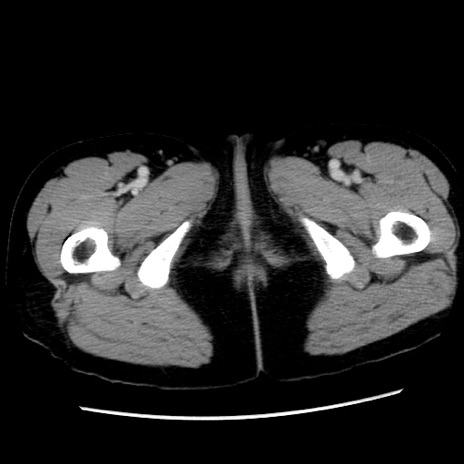

症例10(横断像)

【症例】 50歳代女性

【主訴】 腹痛

【現病歴】前日生レバーを食べた。今朝に排便あり。 昼前に突然発症の腹痛を生じ、当院救急外来を受診した。

【既往歴】 子宮筋腫にてで子宮全摘後

【身体所見】 意識清明、腹部:平坦、軟、下腹部やや左を中心に圧痛・反跳痛あり、筋性防御あり

【データ】WBC 7800、CRP 0.07